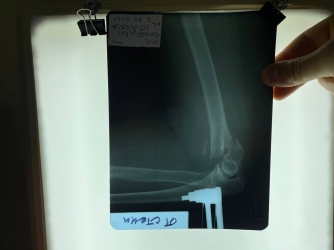

- Пациентка попала в больницу неотложных состояний с тяжелым внутрисуставным перелом плечевой кости, - сообщают в ТМО «Многопрофильная больница интенсивных методов лечения. - Врачи успешно провели сверхсложную операцию. С помощью аппарата наружной фиксации, без разрезов через небольшие проколы, провели стержни в мелкие костные фрагменты и надежно их зафиксировали. Операция была малоинвазивной. На общее состояние женщины она никак не отразилась. Обошлось без кровопотери, разрезов и крупных рубцов. Благодаря этому трудностей в дальнейшей разработке локтевого сустава не предвидится!

– Это высший пилотаж! – Отметил работу врачей доктор медицинских наук Петр Белинский. - Так методом внеочагового остеосинтеза никто не владеет, к сожалению.